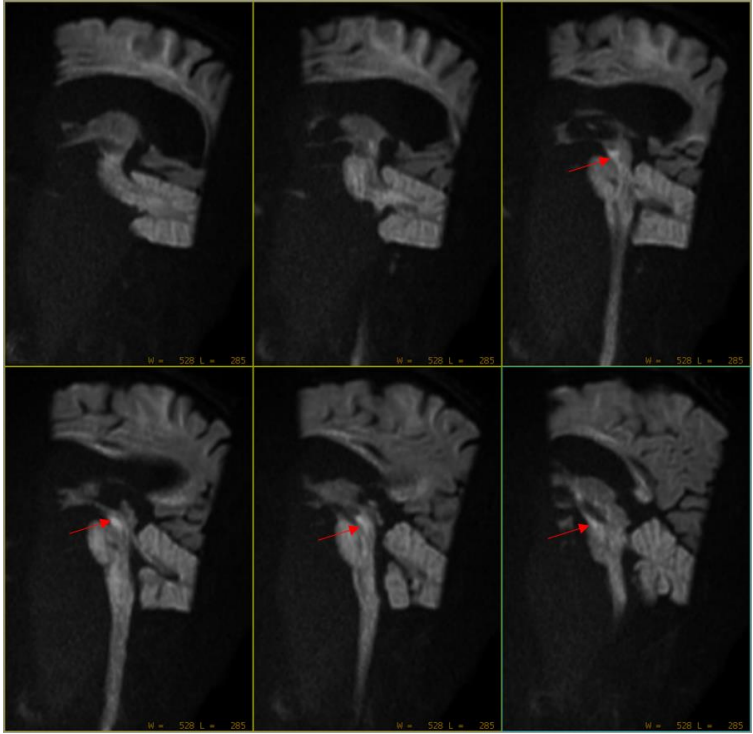

可见中脑位置似乎有异常稍高信号灶。但是患者开始出现运动。此时留给技术组老师的时间已经不多了。 然而,经过简单有效沟通后(扯着嗓子喊了一声:别动),扫描继续。 Sag DWI b=1000s/mm2,层厚3mm,0间隔扫描,扫描时间36秒:

随着b值升高,中脑病灶信号增高,ADC亦见明显低信号 大海捞针最终找到了病灶。 临床不再因MRI未见异常而不知如何是好。 四、常规AX DWI为什么难以发现脑干梗死 最近几年,陆陆续续有几篇SCI文章提示,AX DWI难以发现脑干梗死,必要时建议增加SAG 或者COR DWI,甚至使用更高b值,便于发现更隐匿的梗死病灶。